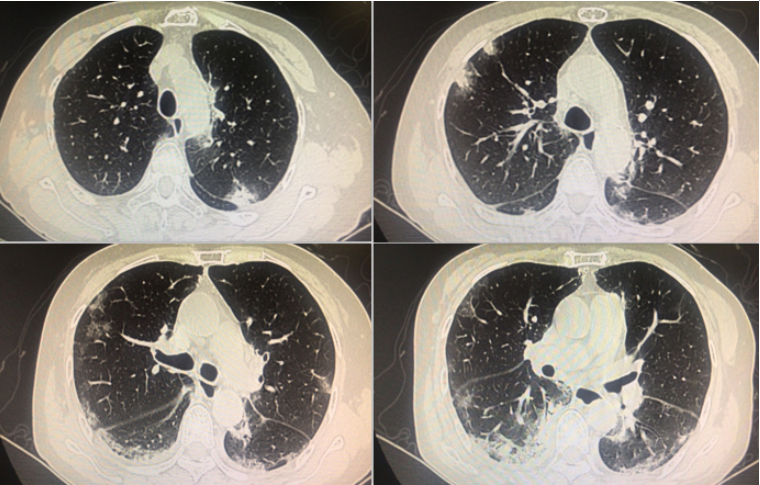

原发性肺念珠菌病男性55岁间断咳嗽8年发热8天加重2天

图片尺寸695x412